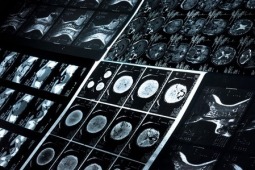

Przyczyny zgonu u chorych na nowotwory złośliwe narządów głowy i szyi w trakcie wieloletniej obserwacji

Dzięki postępowi w dziedzinie radioterapii i chemioterapii chorych na nowotwory złośliwe narządów głowy i szyi obserwujemy wysokie odsetki wyleczeń. Obecne wytyczne kładą duży nacisk na monitorowanie chorych pod kątem wczesnego wykrycia wznowy choroby, która najczęściej pojawia się w okresie pierwszych trzech lat od zakończenia pierwotnego leczenia. Prezentowane badania poddaje analizie odległe przyczyny zgonu w populacji chorych na nowotwory narządów głowy i szyi, u których w przeszłości zastosowano leczenie radykalne.